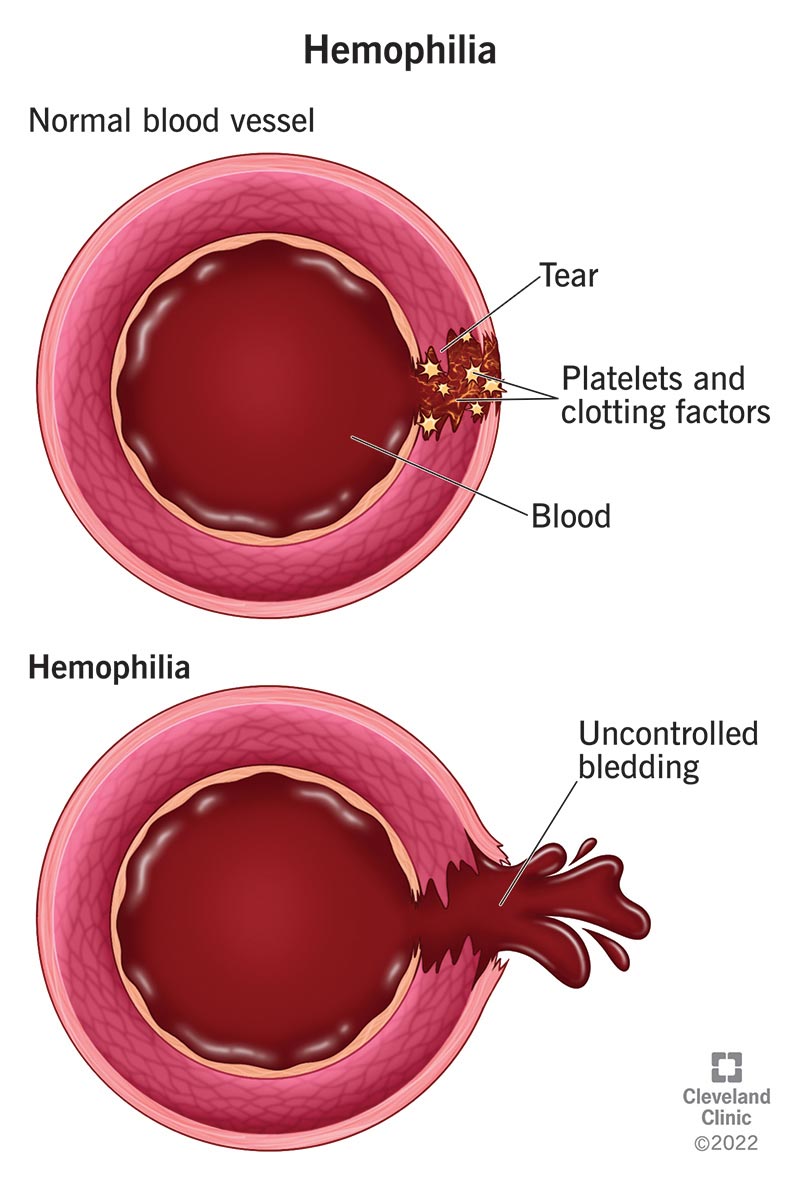

What Is Hemophilia?